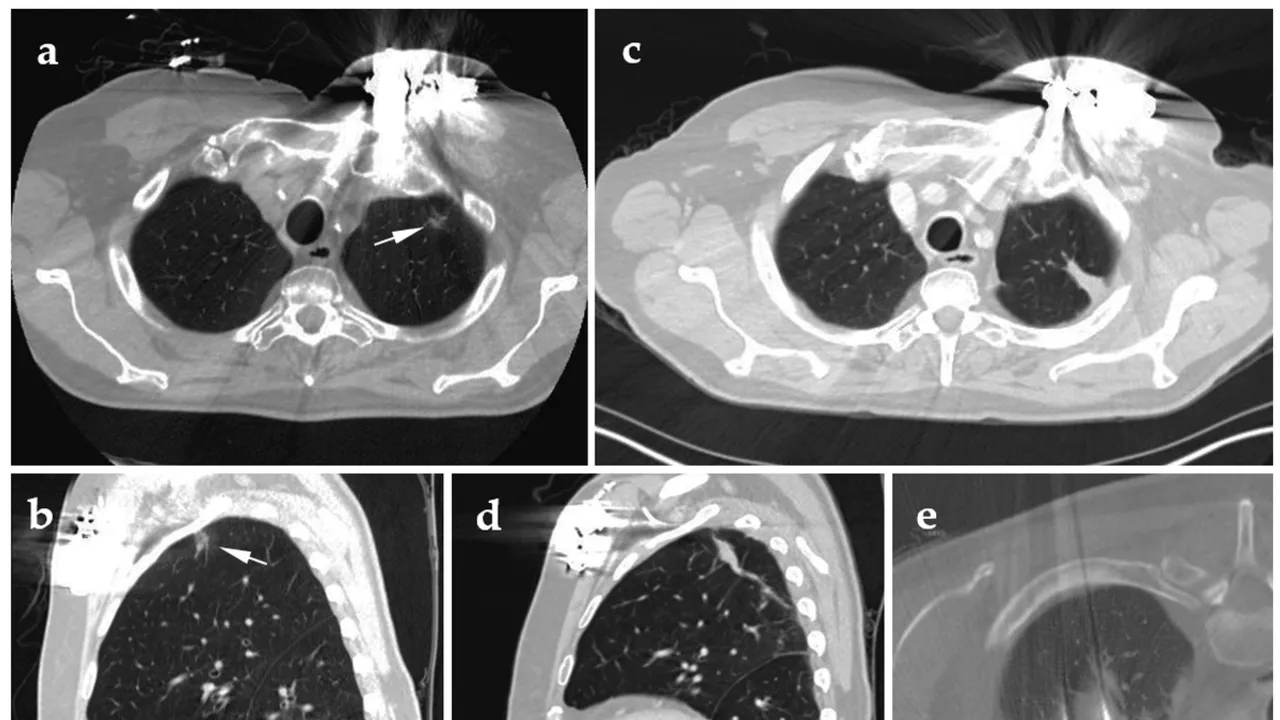

From bnnbreaking.com

Groundbreaking Endoscopic Ablation of Lung Cancer Performed in Belgium Endoscopic Ablation Treatment Radiofrequency ablation (rfa) under endoscopic ultrasound (eus) guidance has been developed and utilized over the last. More than any other area of gastrointestinal endoscopy, ablation therapy has incorporated numerous imaging and technology. Several percutaneous and endoscopic ultrasound (eus) guided ablative techniques have been explored for the. In this review, we aim to provide an overview of the current state of. Endoscopic Ablation Treatment.